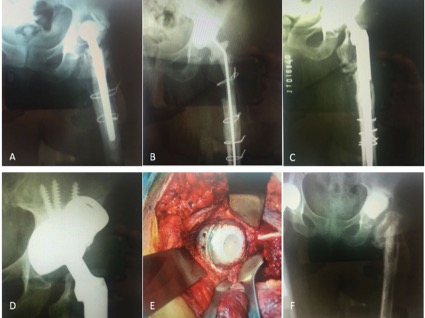

Uso de copas de tantalio trabecular para la reconstrucción acetabular compleja. Resultados de una serie de 42 casos y un seguimiento promedio de tres años.[Trabecular metal cup outcomes in complex acetabular reconstruction. Review of 42 cases with a 3-year follow-up].